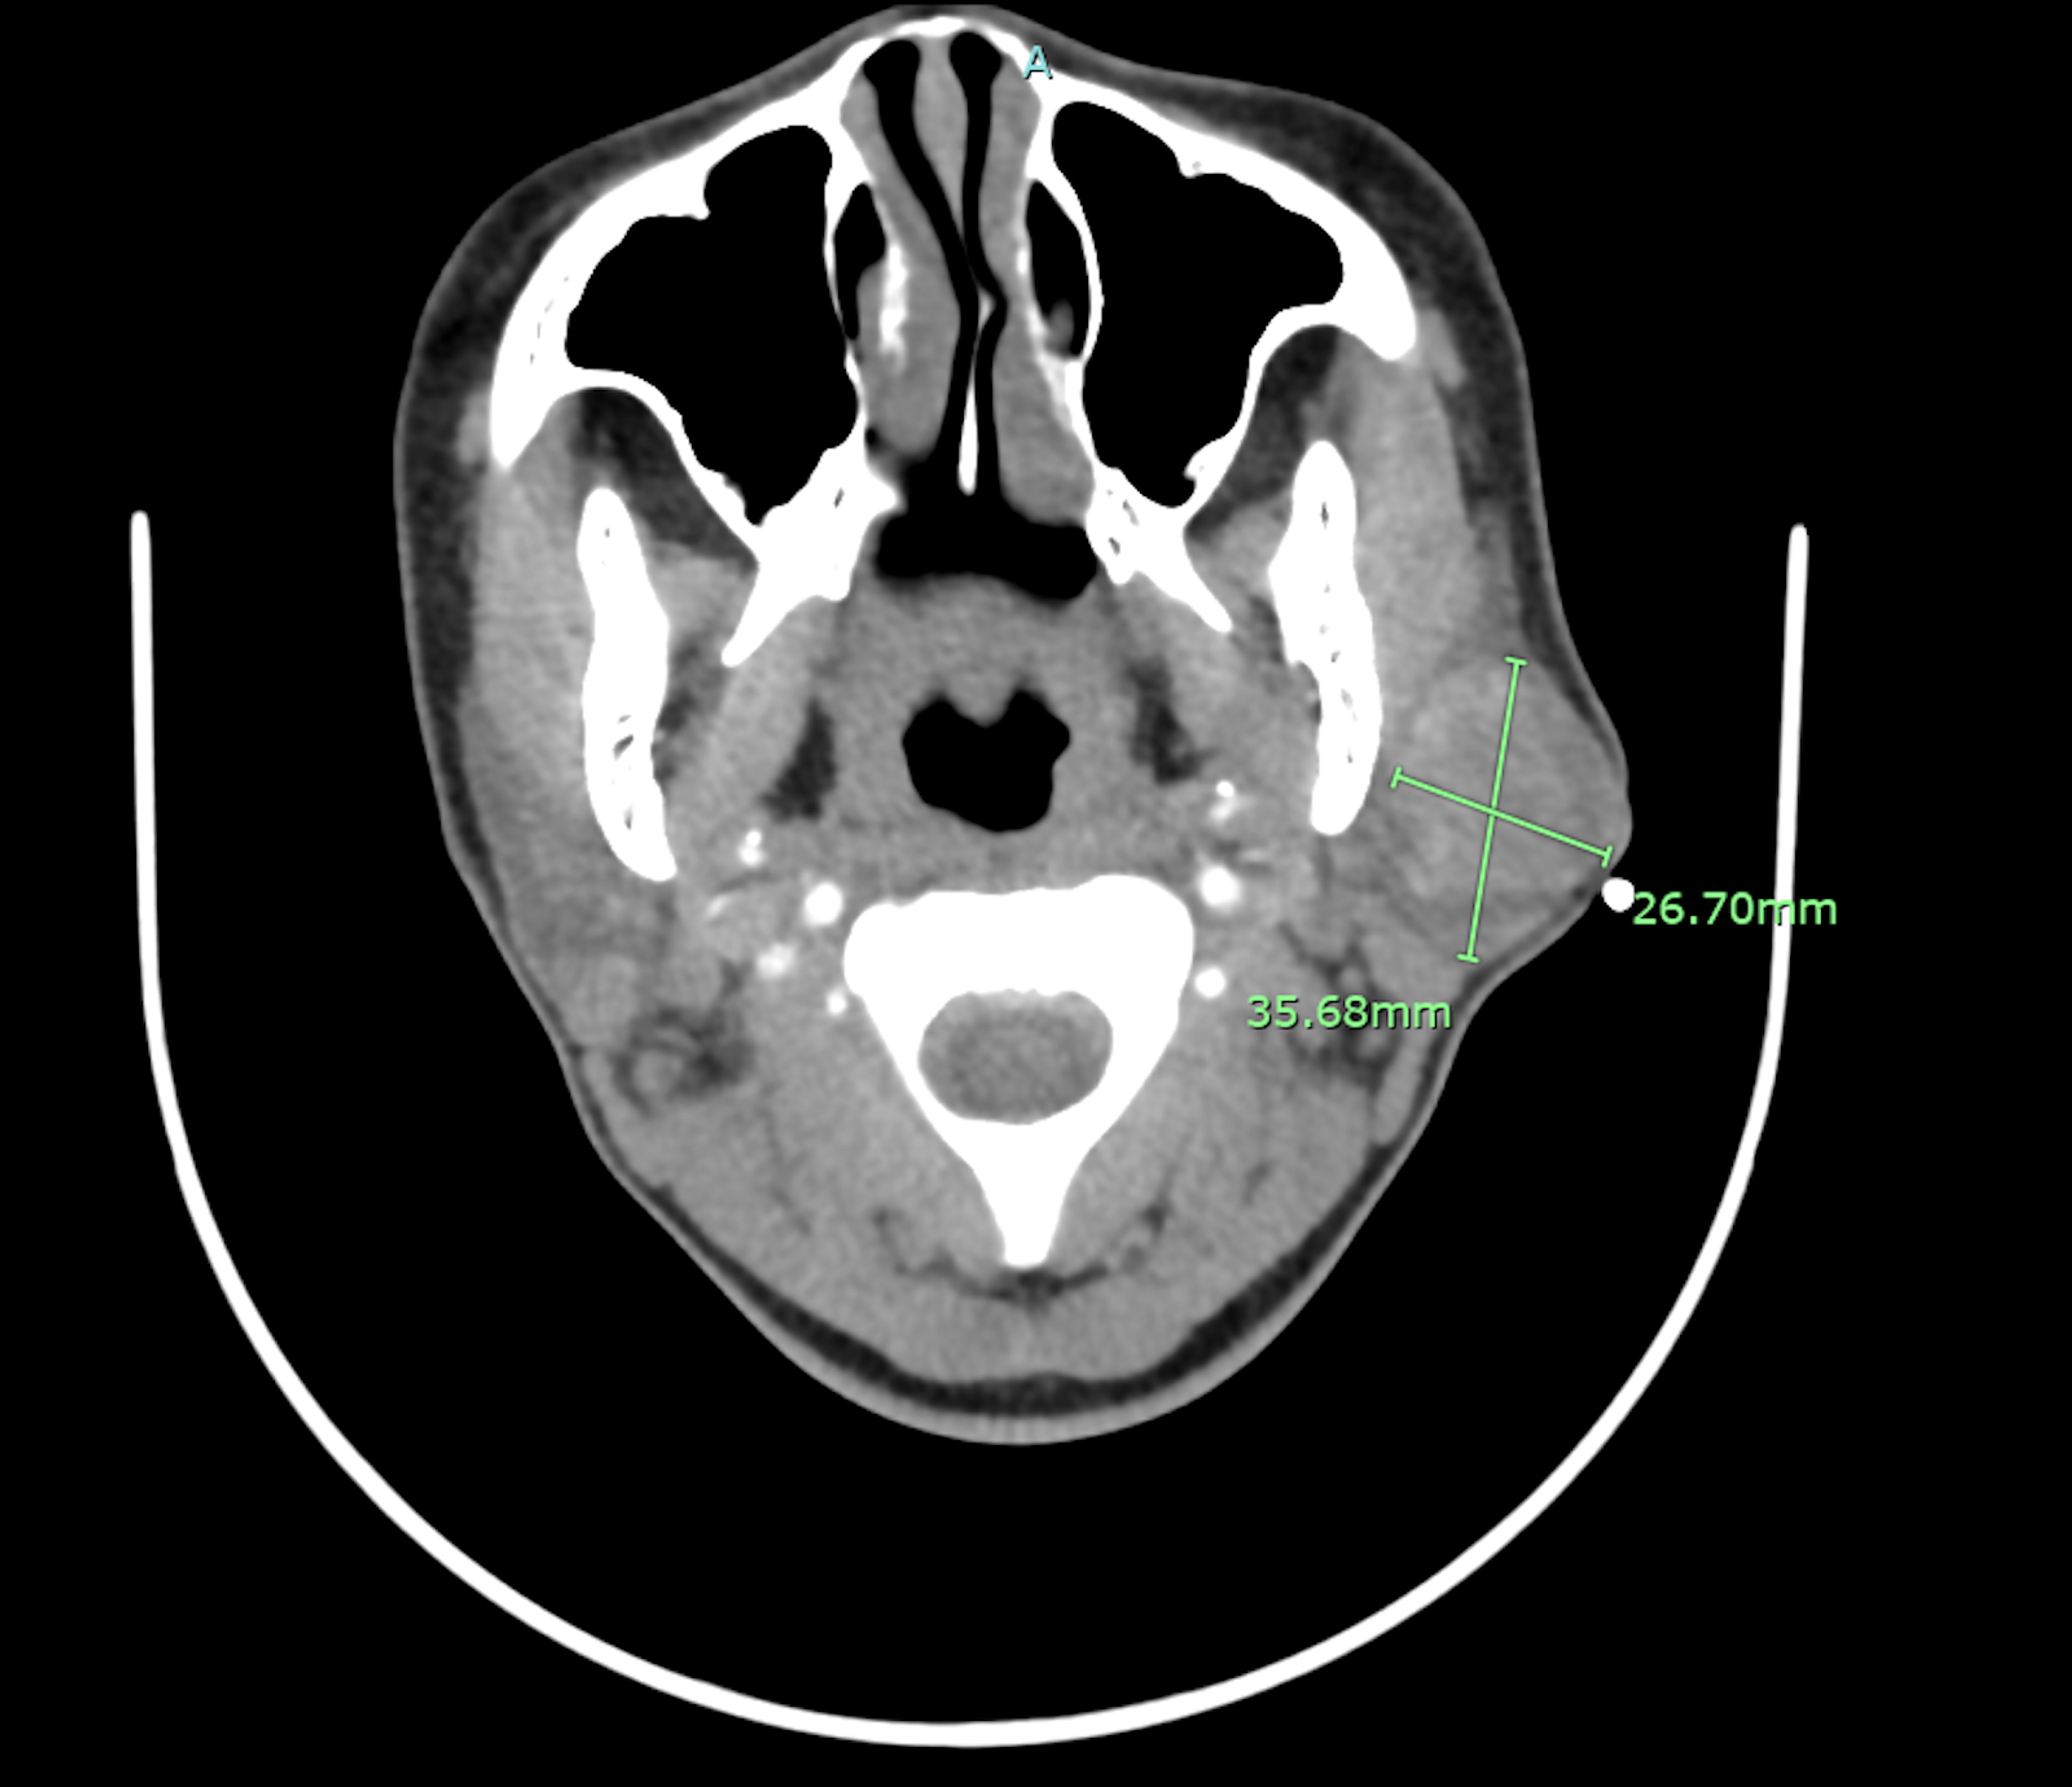

What Is A Glandular Tumor. Salivary gland tumors are rare. adenocarcinoma is a very common type of cancer that starts either in the skin or in one of the body cavities. There are two broad categories of endocrine tumors:. adenocarcinoma is a type of cancer that affects glands and glandular tissues. an endocrine tumor can form when abnormal cells in an endocrine gland or organ arise and grow uncontrollably. salivary gland tumors are growths of cells that start in the salivary glands. It can affect many parts of. These are the organs and tissues, respectively, that produce substances ranging. when you find a cancerous lymph node that’s just embedded in a salivary gland, but the gland itself appears unaffected, it almost always comes from a skin. the accumulating cells form a mass called a tumor. adenocarcinoma is a type of cancer that starts in glands that line the insides of the organs, which is why it can affect. The tumor can grow to invade nearby tissue and can spread.